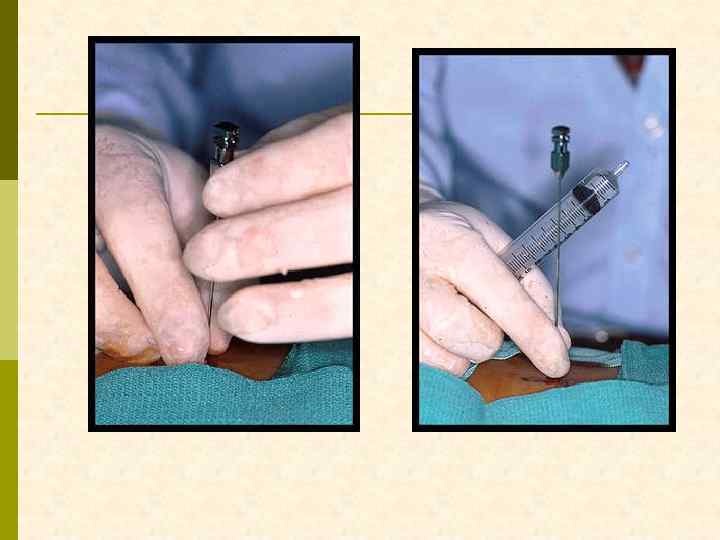

ВВЕДЕНИЕ БИОПСИОННОЙ ИГЛЫ В РЕТРОПЕРИТОНЕУМ

БИОПТАТ ПОМЕЩАЕТСЯ В РАСТВОР КОНСЕРВАНТА